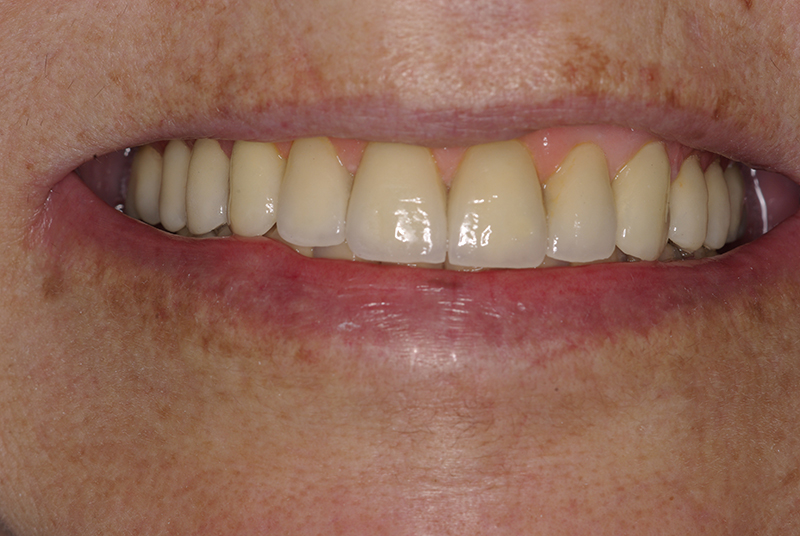

Na Clínica Pontes Odontologia, somos referência em implantes dentários em Fortaleza, oferecendo tratamentos de alta qualidade e tecnologia de ponta. Os implantes dentários são estruturas de titânio posicionadas cirurgicamente no osso maxilar ou mandibular para substituir as raízes dos dentes ausentes. Essa técnica permite a fixação de próteses personalizadas, restaurando a função mastigatória, a estética e a autoestima dos nossos pacientes.

Nosso compromisso é oferecer um tratamento de excelência, com profissionais especializados e tecnologia de última geração para implantes dentários em Fortaleza. Venha nos visitar e descubra por que a Clínica Pontes Odontologia é referência em implantes dentários em Fortaleza, devolvendo sorrisos e qualidade de vida aos nossos pacientes.